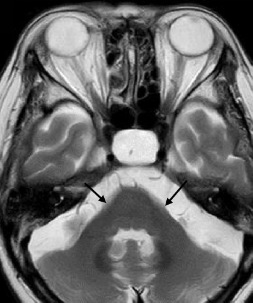

The MRI features of Alexander disease in people with later age of onset (ie, juveniles and adults) do not typically include frontal white matter changes and are instead characterized by brainstem, cerebellum, and spinal cord abnormalities; these patients may not exhibit the same MRI features that support a diagnosis in people with earlier age of onset.4,16,52

MRI findings in people with onset in adulthood are characterized by:

- Atrophy and changes in signal intensity in the cerebellum, medulla oblongata, and upper spinal cord, with variable supratentorial periventricular white matter abnormalities4

- A pattern of prominent atrophy involving the medulla oblongata and cervical spinal cord with sparing of the lower pons (ie, “tadpole sign”)8,53

An additional imaging pattern characterized by bilateral symmetric hyperintensity on T2-weighted imaging involving the central inferior olivary nucleus, the pyramids, and the cuneate and gracile fascicles, with sparing of the peripheral inferior olivary nucleus and inferior peduncle (termed the “chipmunk sign”), is a common feature in people with Alexander disease regardless of age of onset.62